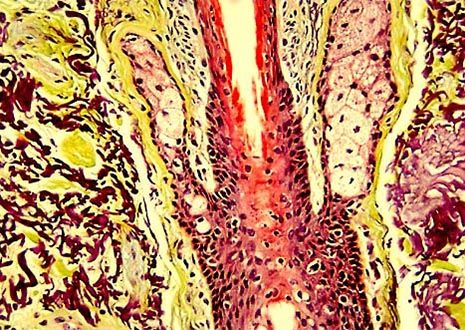

Skin Hair Shaft with Sebaceous Glands

Hair does not exist and grow alone, but is part of the pilosebaceous system, which also includes follicles, papillae, and sebaceous glands. A typical human has approximately 100,000 hairs on his or her scalp and loses about 50 to 100 strands a day.